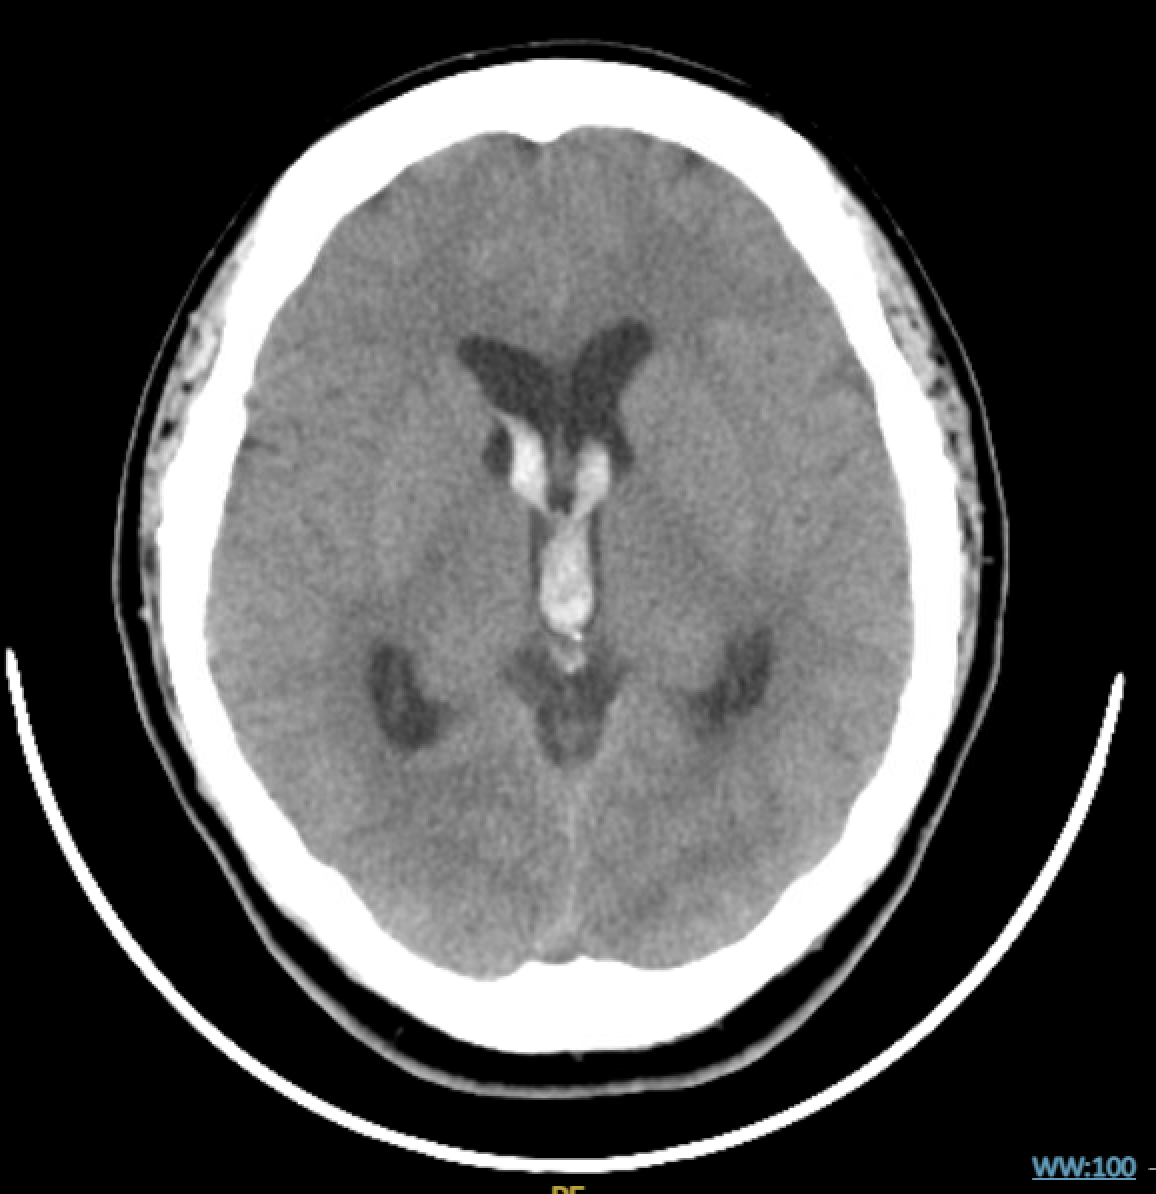

Noncontrast CTH, Axial View. See hyperdensity in the lateral ventricles. Note the absence of intraparenchymal hemorrhage.